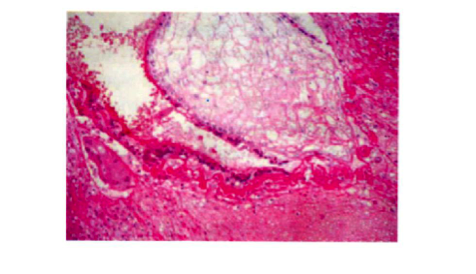

Bệnh nhân nữ 30 tuổi, PARA 1011, tiền sử mổ TNTC ở vòi tử cung bên phải; kinh nguyệt đều, vòng kinh 30 ngày. Bệnh nhân bị chậm kinh một tháng, đau âm ỉ hạ sườn phải 1 tháng, không ra máu âm đạo. Bệnh viện Phụ Sản Hà Nội nghi u nguyên bào nuôi và chuyển đến Bệnh viện Phụ Sản Trung ương. Xét nghiệm β-hCG: 73.047 IU/L; siêu âm Doppler: dưới gan có hình ảnh túi thai d=35mm, chiều dài phôi: 22mm, tim thai (+). Chẩn đoán thai dưới gan. Nội soi: khối thai 3cm nằm ở cạnh phải túi mật, gần tĩnh mạch cửa. Bóc khối thai và cầm máu bằng dao điện và chèn Spongel. Xét nghiệm β-hCG sau 72 giờ: 14.109 IU/L. Giải phẫu bệnh: gai nhau điển hình.

Hình 2. Hình ảnh nguyên bào nuôi ở nhu mô gan (BA1) |